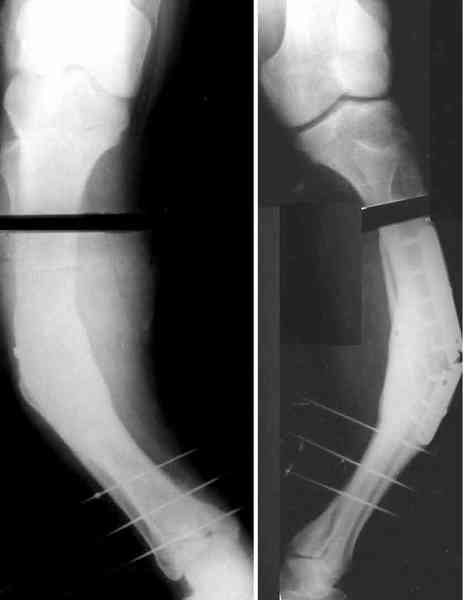

Для продолжения темы - несколько картинок.

Пациент 30 лет, лет пять назад оперирован по поводу перелома голени пластиной. Находясь на героине, нарушил режим, пошел, сломал и ногу и

пластину, но перелом сросся.

В приложении - внешний вид и рентген.

Аппарат с шарнирами, чрескожная остеотомия, устранение угла.

Аппарат можно использовать как окончательный фиксатор. Но можно убрать винты и сделать интрамедуллярный остеосинтез сразу после

восстановления оси.

Александр, как раз уровень остеотомии подробнее - на вершине деформации? Там Сломанная пластина.

Там не винты (может, плохо видно), а сломанная пластина, вросшая в кость.

Ну, например, на уровне перелома пластинки. Можно пересечь часть кости, не прилежащую к пластинке, затем надломить остальное.

Пластинку и винты мне удалось разглядеть только на профильной проекции, точнее, трехчетвертной, судя по виду коленного сустава (правый снимок). На фасной - вообще не могу разобрать, где она :( Но, в конце концов, можно и не видя ее сказать, что уровень остеотомии может быть и другим, ниже или выше пластинки, придется только компенсировать смещение по ширине, которое появится при полном устранении угла не на вершине.